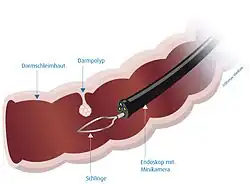

Das flexible Koloskop hat einen Durchmesser von etwa 1 cm und eine Länge von zirka 1,2 Metern. Zumeist wird heute ein Video-Koloskop verwendet, das an der Spitze eine Kamera besitzt und das Bild auf einen Monitor überträgt. So ist es möglich, dass der Patient die Untersuchung mitverfolgen kann. Das Koloskop ist mit einer Absaugvorrichtung ausgerüstet, um flüssige Stuhlreste und Spülflüssigkeit absaugen zu können. Ein Arbeitskanal ermöglicht das Einführen von kleinen Instrumenten (Zangen und Schlingen), mit denen kleine Gewebeproben bzw. Polypen entnommen werden können.

Polypen

Polypen sind makroskopisch sichtbare, meist gestielte Ausstülpungen der Mukosa. Im Laufe mehrerer Jahre können sie entarten und zu Dickdarmkrebs (siehe auch Adenom-Karzinom-Sequenz) führen, und sie werden deshalb (auch im Rahmen von Vorsorgekoloskopien) in derselben Sitzung entfernt.